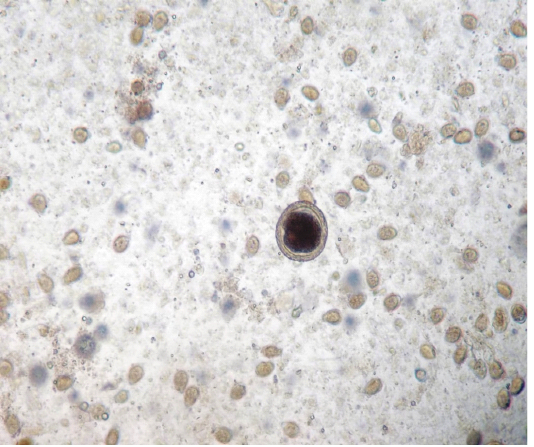

Figure 1

Egg of Toxocara vitulorum and Oocysts of Eimeria bareillyi (10x)